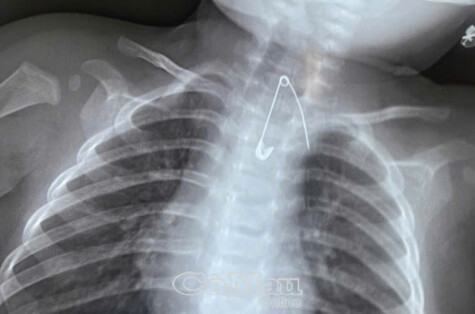

Hình ảnh chụp X- Quang dị vật kim tây mắc ở thực quản bé Đ.

Qua thăm khám lâm sàng và các xét nghiệm cận lâm sàng, các bác sĩ phát hiện một kim tây nằm trong mô mềm, ở vị trí 1/3 trên thực quản, rất gần động mạch chủ, tiềm ẩn nguy cơ biến chứng nghiêm trọng. Ê-kíp bác sĩ đã tiến hành can thiệp khẩn cấp và lấy dị vật ra an toàn.

Bác sĩ Ninh Thị Ly, Trưởng phòng Công tác xã hội Bệnh viện Sản - Nhi Cà Mau cho biết: “Bé 7 tháng tuổi đã nuốt kim tây vào đường tiêu hóa. Đầu mũi kim nằm rất gần động mạch chủ nên quá trình can thiệp đòi hỏi sự cẩn trọng và khéo léo để tránh gây tổn thương nguy hiểm cho bé”.